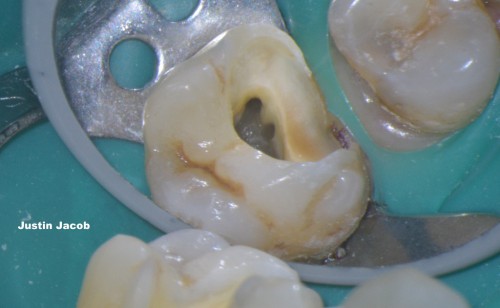

Sealer dynamics helped not to leave an untreated canal in Mesio-buccal root

Justin Jacob